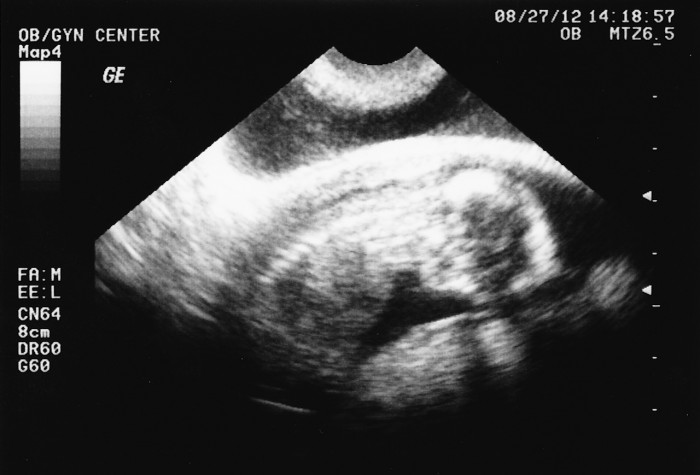

2012-08-27-Ultrasound-06-web